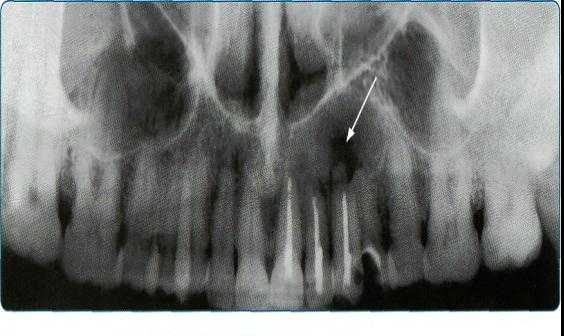

5. Ортопантомография

Панорамная зонография, или, как ее чаще называют, ортопантомография, явилась своего рода революцией в рентгенологии челюстно-лицевой области и не имеет себе равных по ряду показателей (обзор большого отдела лицевого черепа в идентичных условиях, минимальная лучевая нагрузка, малые затраты времени на исследование).

Панорамная зонография позволяет получить плоское изображение изогнутых поверхностей объемных областей, для чего используют вращение рентгеновской трубки и кассеты.

Преимуществом ортопантомографии является возможность демонстрировать межчелюстные контакты, оценивать Результаты воздействия межчелюстной нагрузки по состоянию замыкающих пластинок лунок и определять ширину периодонтальных путей.

Ортопантомограммы демонстрируют взаимоотношения зубов верхнего ряда с дном верхнечелюстных пазух и позволяют выявить в нижних отделах пазух патологические изменения одонтогенного генеза.

Особенно важно использовать ортопантомографию в детской стоматологии, где она не имеет конкурентов в связи с низкими дозами облучения и большим объемом получаемой информации. В детской практике ортопантомография помогает диагностировать переломы, опухоли, остеомиелит, кариес, периодонтиты, кисты, определять особенности прорезывания зубов и положение зачатков.